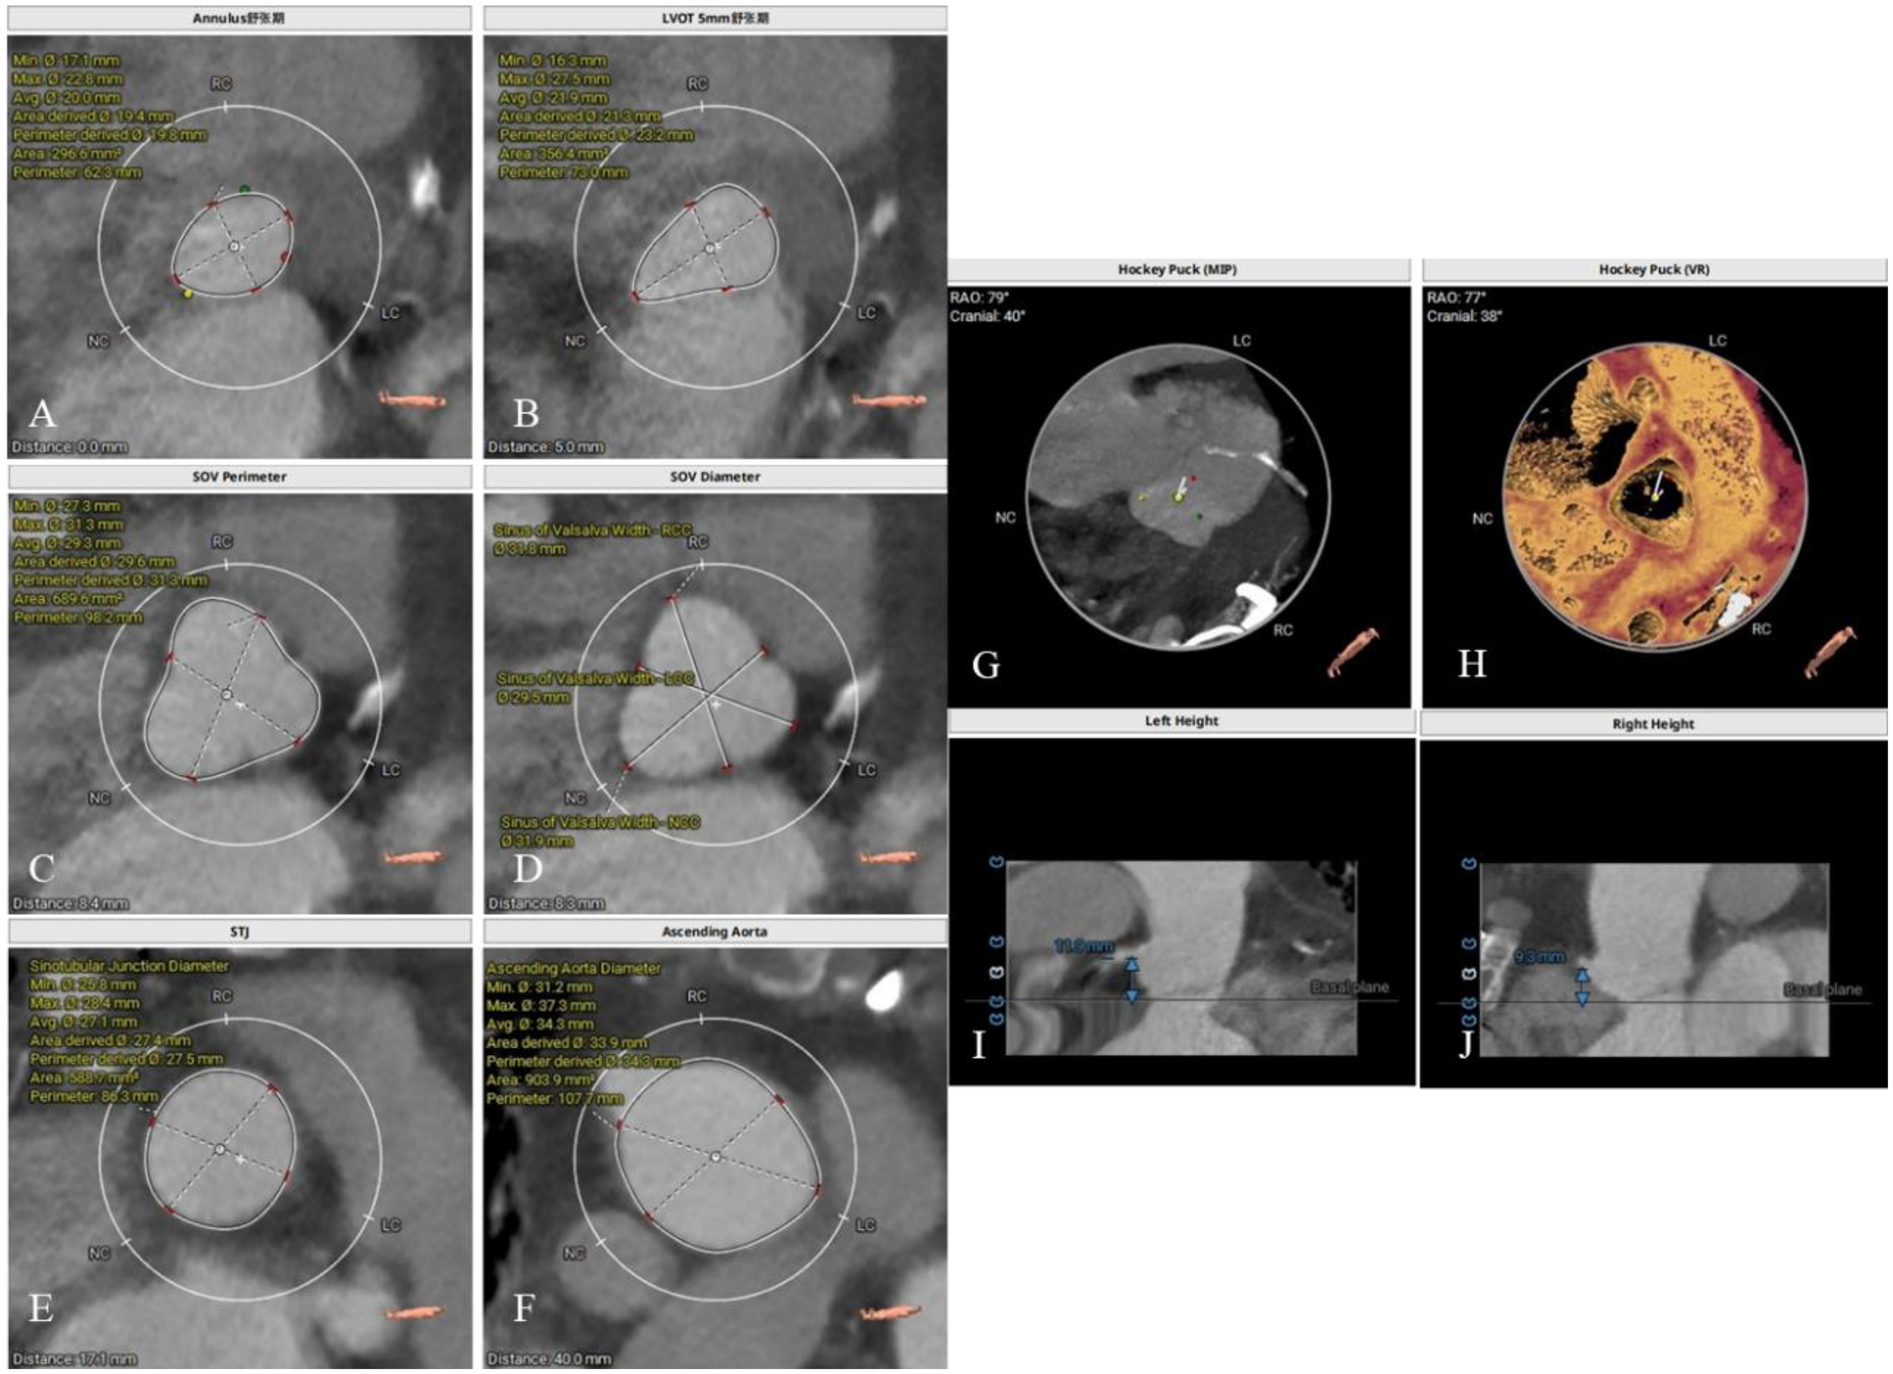

Preoperative CT evaluation

The patient had a regurgitant tri-leaflet aortic valve with a normally shaped, elliptical-like annulus. The valve leaflets showed no thickening, calcification, or commissural fusion. The annular circumference measured 62.3 mm, with a circumference-derived diameter of 19.8 mm. The diameter of the left ventricular outflow tract (LVOT) exceeded that of the annulus during diastole, giving it an overall funnel-like appearance. The supra-annular region was nearly cylindrical, posing significant challenges for anchoring and elevating the risk of valve migration. Specific measurement data can be found in Figure 2. According to current guidelines, in patients with AR, larger self-expanding valves are generally preferred compared with those used for aortic stenosis, in order to achieve stronger radial force and anchoring. The guidelines recommend an oversizing ratio of prosthetic valve diameter relative to the annular diameter of 15%–30%. The valve selection in this case followed these principles. Based on the preoperative CT evaluation and the absence of significant calcification of the native aortic valve, a Taurus Trio 25 valve (size: 28 mm) was ultimately implanted via the right femoral artery approach to achieve optimal radial support and anchoring stability. The Taurus Trio TAVR system is designed on the basis of the JenaValve Trilogy transcatheter heart valve technology (4). Its unique locator elements enable secure anchoring even in the absence of calcification, effectively preventing valve migration toward the LVOT while ensuring precise coaptation with the native leaflets. This design promotes long-term hemodynamic stability and preserves the possibility of future percutaneous coronary interventions (PCI).

Figure 2

Preoperative CT evaluation. (A) Annular circumference diameter: 19.8 mm; (B) outflow tract circumference diameter: 23.2 mm; (C) sinus of valsalva circumference diameter: 31.3 mm; (D) sinus of valsalva diameter: 31.8 mm, 29.5 mm, 31.9 mm; (E) sinutubular junction circumference diameter: 27.5 mm; (F) aortic circumference diameter 4 cm above the annulus: 34.3 mm; (G,H) no significant calcification observed in the annulus and leaflets; (I) height of the left coronary artery ostium: 11.9 mm; (J) height of the right coronary artery ostium: 9.3 mm.